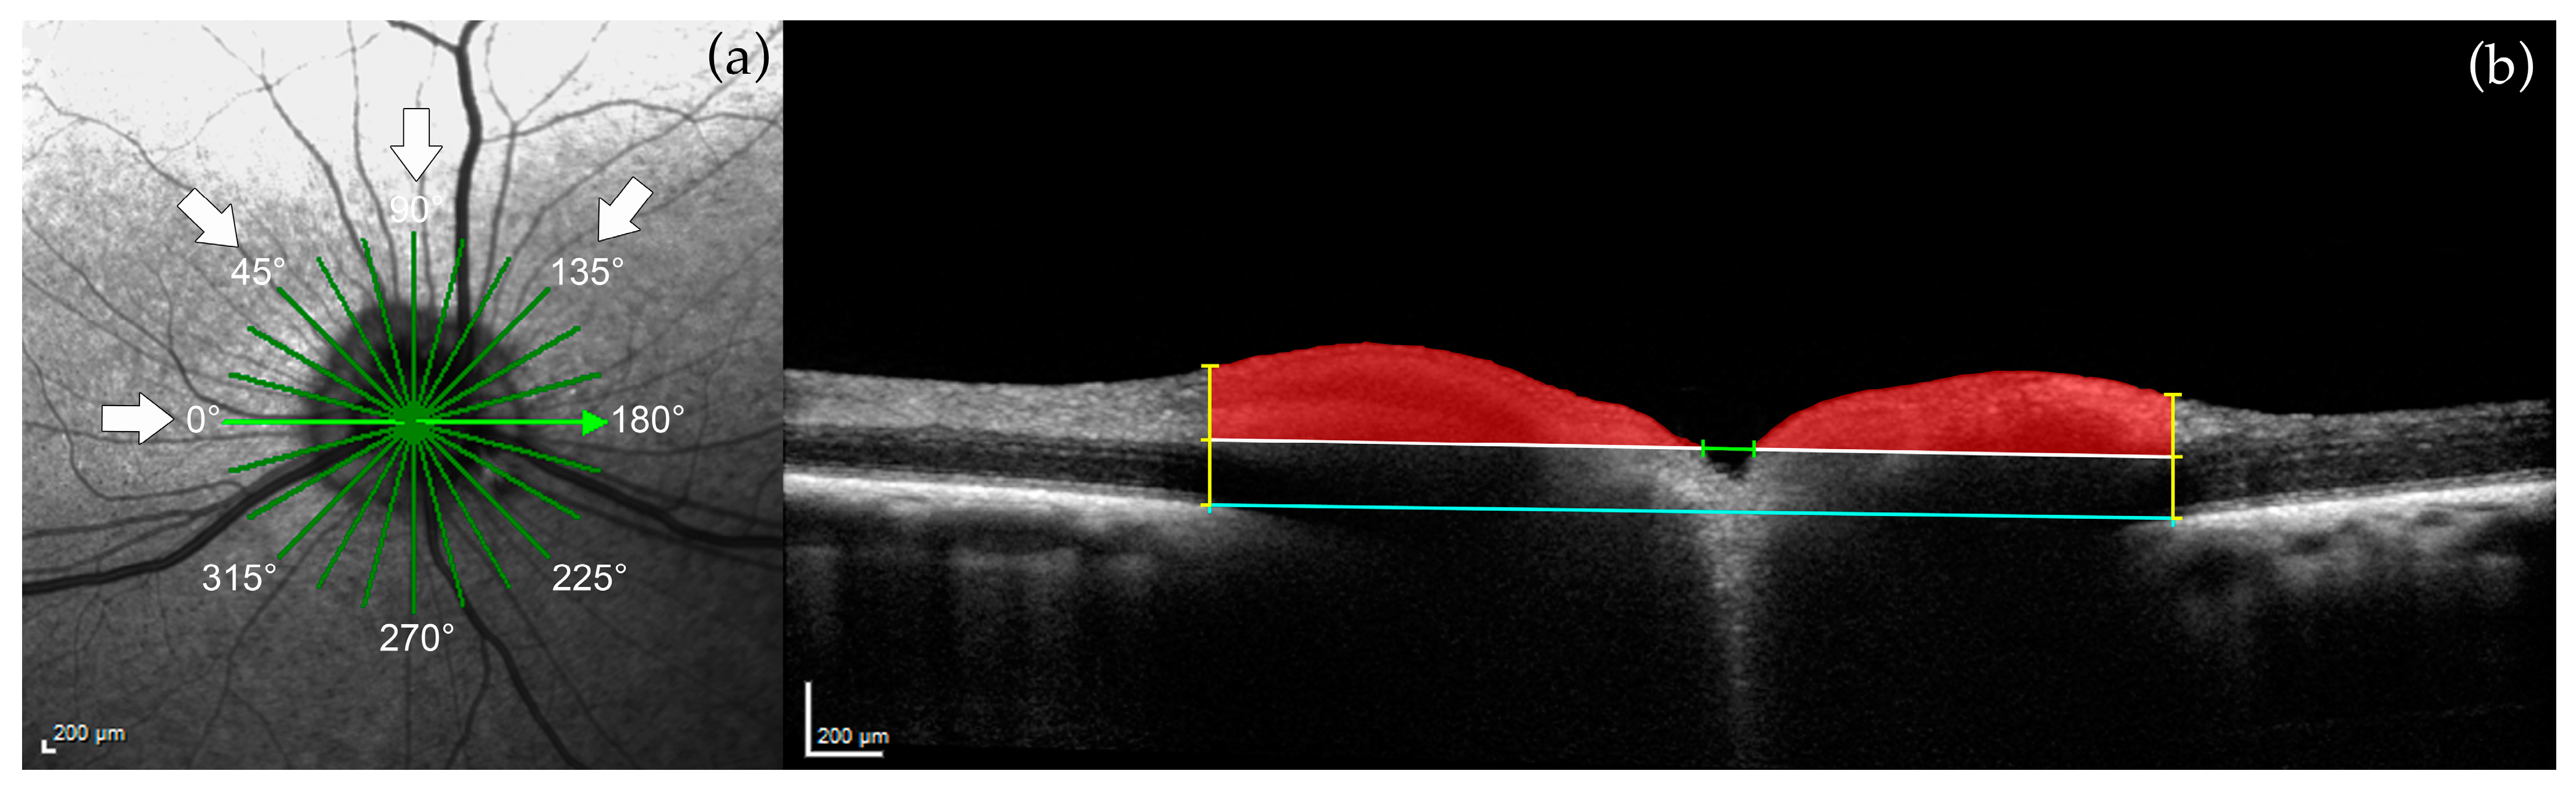

2.3.1. Optic Nerve Head (ONH) Measurements

3.1. Optic Nerve Head